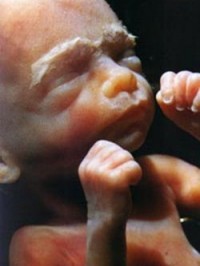

Ваша дитина: вага і ріст на 25 тижні.

- На даний момент, можна сміливо грати з вашим майбутнім дитиною в дитячу гру «Ладушки», оскільки ручки немовляти повністю розроблені і більшу частину неспання зайняті обмацуванням простору матки в темряві.

- З огляду на те, що мозок і нервові закінчення досить розвинені зараз, малюк може відчути дотик, і тикання татуся пальцем вам в живіт в тому числі.

- Ноги і руки дитини виросли до своїх остаточних пропорцій (як при народженні), але все одно вони залишаються коротенькими. Так що не лякайтеся, коли ручки новонародженого ледь обіймуть його талію.

- Ніздрі дитини, сплющені досі, тепер щосили практикують дихання через ніс.

- Структура хребта вже складається з 150 суглобів, 33 дисків і близько 1000 зв'язок. Чи можете ви повірити, що ви виношуєте в собі таку складну ієрархію?

- Капіляри або крихітні кровоносні судини надають раніше напівпрозорої шкірі рожеве світіння. Кровоносні судини в легенях також розвиваються, і ваша дитина тренується дихати через декілька місяців наперед.

- Ваша дитина важить зараз близько 1.4 кг, а його зріст становить 34 см.

Дитина набирає вагу і накопичує підшкірний жир. Продовжує розправлятися його шкіра і він стає світло - рожевим. Особа вже виявляє генетично закладені риси, а кінцівки вже помітно округлюються. Кістковий мозок вже завершив свій розвиток і прийняв на себе функції кровотворення. Сердечко б'ється досить швидко і виробляє до 150 ударів в хвилину. У легких і раніше накопичується сурфактант. Але народився на цьому тижні дитина. все ще не може дихати самостійно, і він буде потребувати спеціального обородуванія.

Вагітність 25 тижнів. Розмір плода.

Дитина росте і вже його зростання становить близько 32 сантиметрів.

Вагітність 25 тижнів. фото плода

Як правило, малюк в цей час активно рухається. Його ворушіння на 25 тижні вагітності стають більш виразними. Плід важить 700-800 грамів, а зріст становить приблизно 30-34 см. Він тепер порівняно великий, при випирання можна розрізнити пяточку, головку або іншу частину тіла малюка. Серцебиття дитини можна послухати, приклавши вухо до живота майбутньої мами. Фото свою дитину в 25 тижнів можна зробити, тільки якщо буде призначено УЗД плоду за життєвими показаннями.